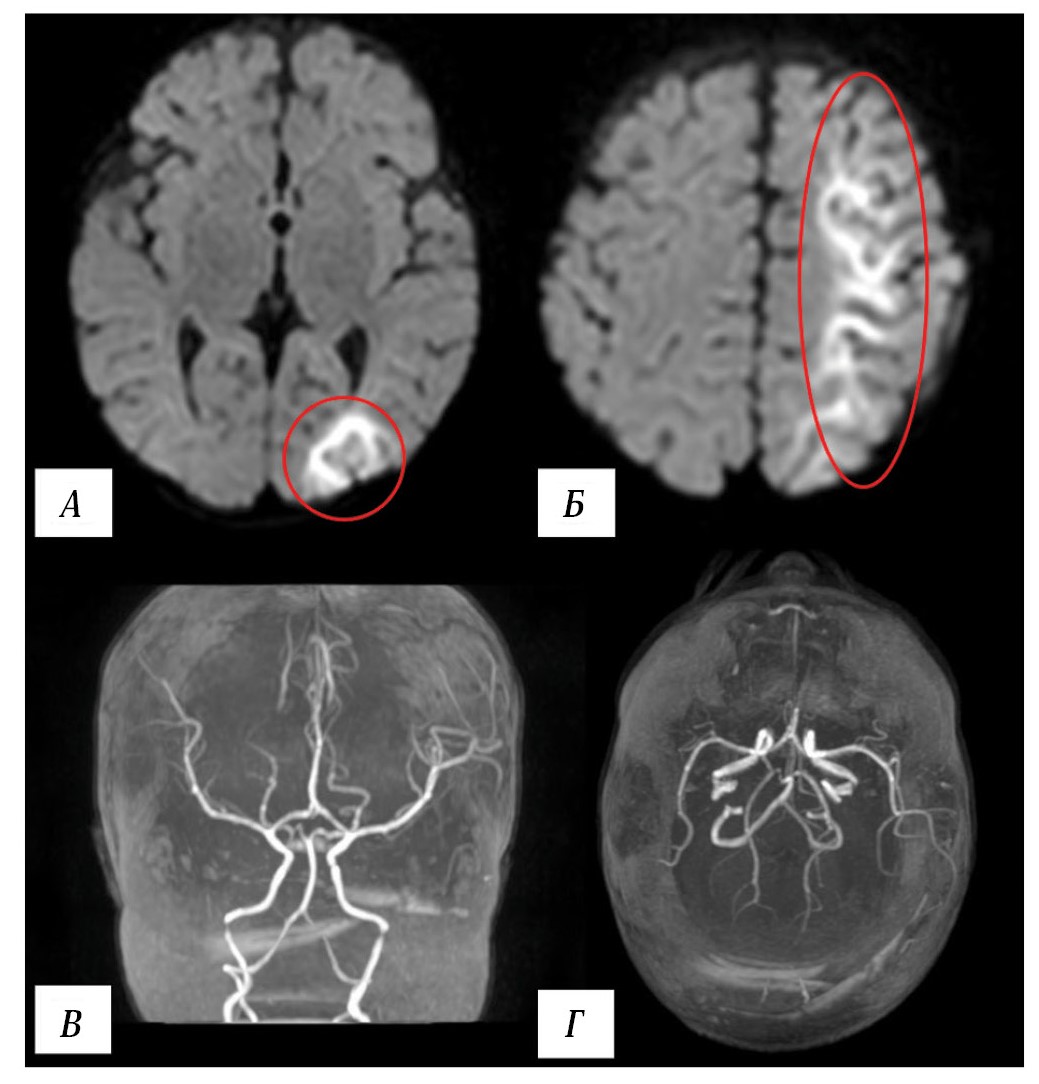

Brain magnetic resonance imaging (MRI) revealed a watershed infarction in the left hemisphere (Fig. 2), while 3D time-of-flight (TOF) MR angiography showed no signal changes in the intracranial arteries.

Fig. 2. Results of patient T. MRI on day 2 postoperatively.

A, B — brain MRI. Diffusion-weighted imaging (DWI), axial view. MRI findings of a watershed infarction in the left hemisphere (within the red oval). C, D — MR angiography, 3D reconstruction. Blood flow in the intracranial arteries of the head is intact.